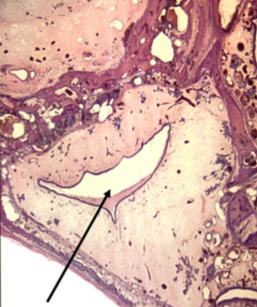

)__ cartilage is in this tracheal ring

hyaline